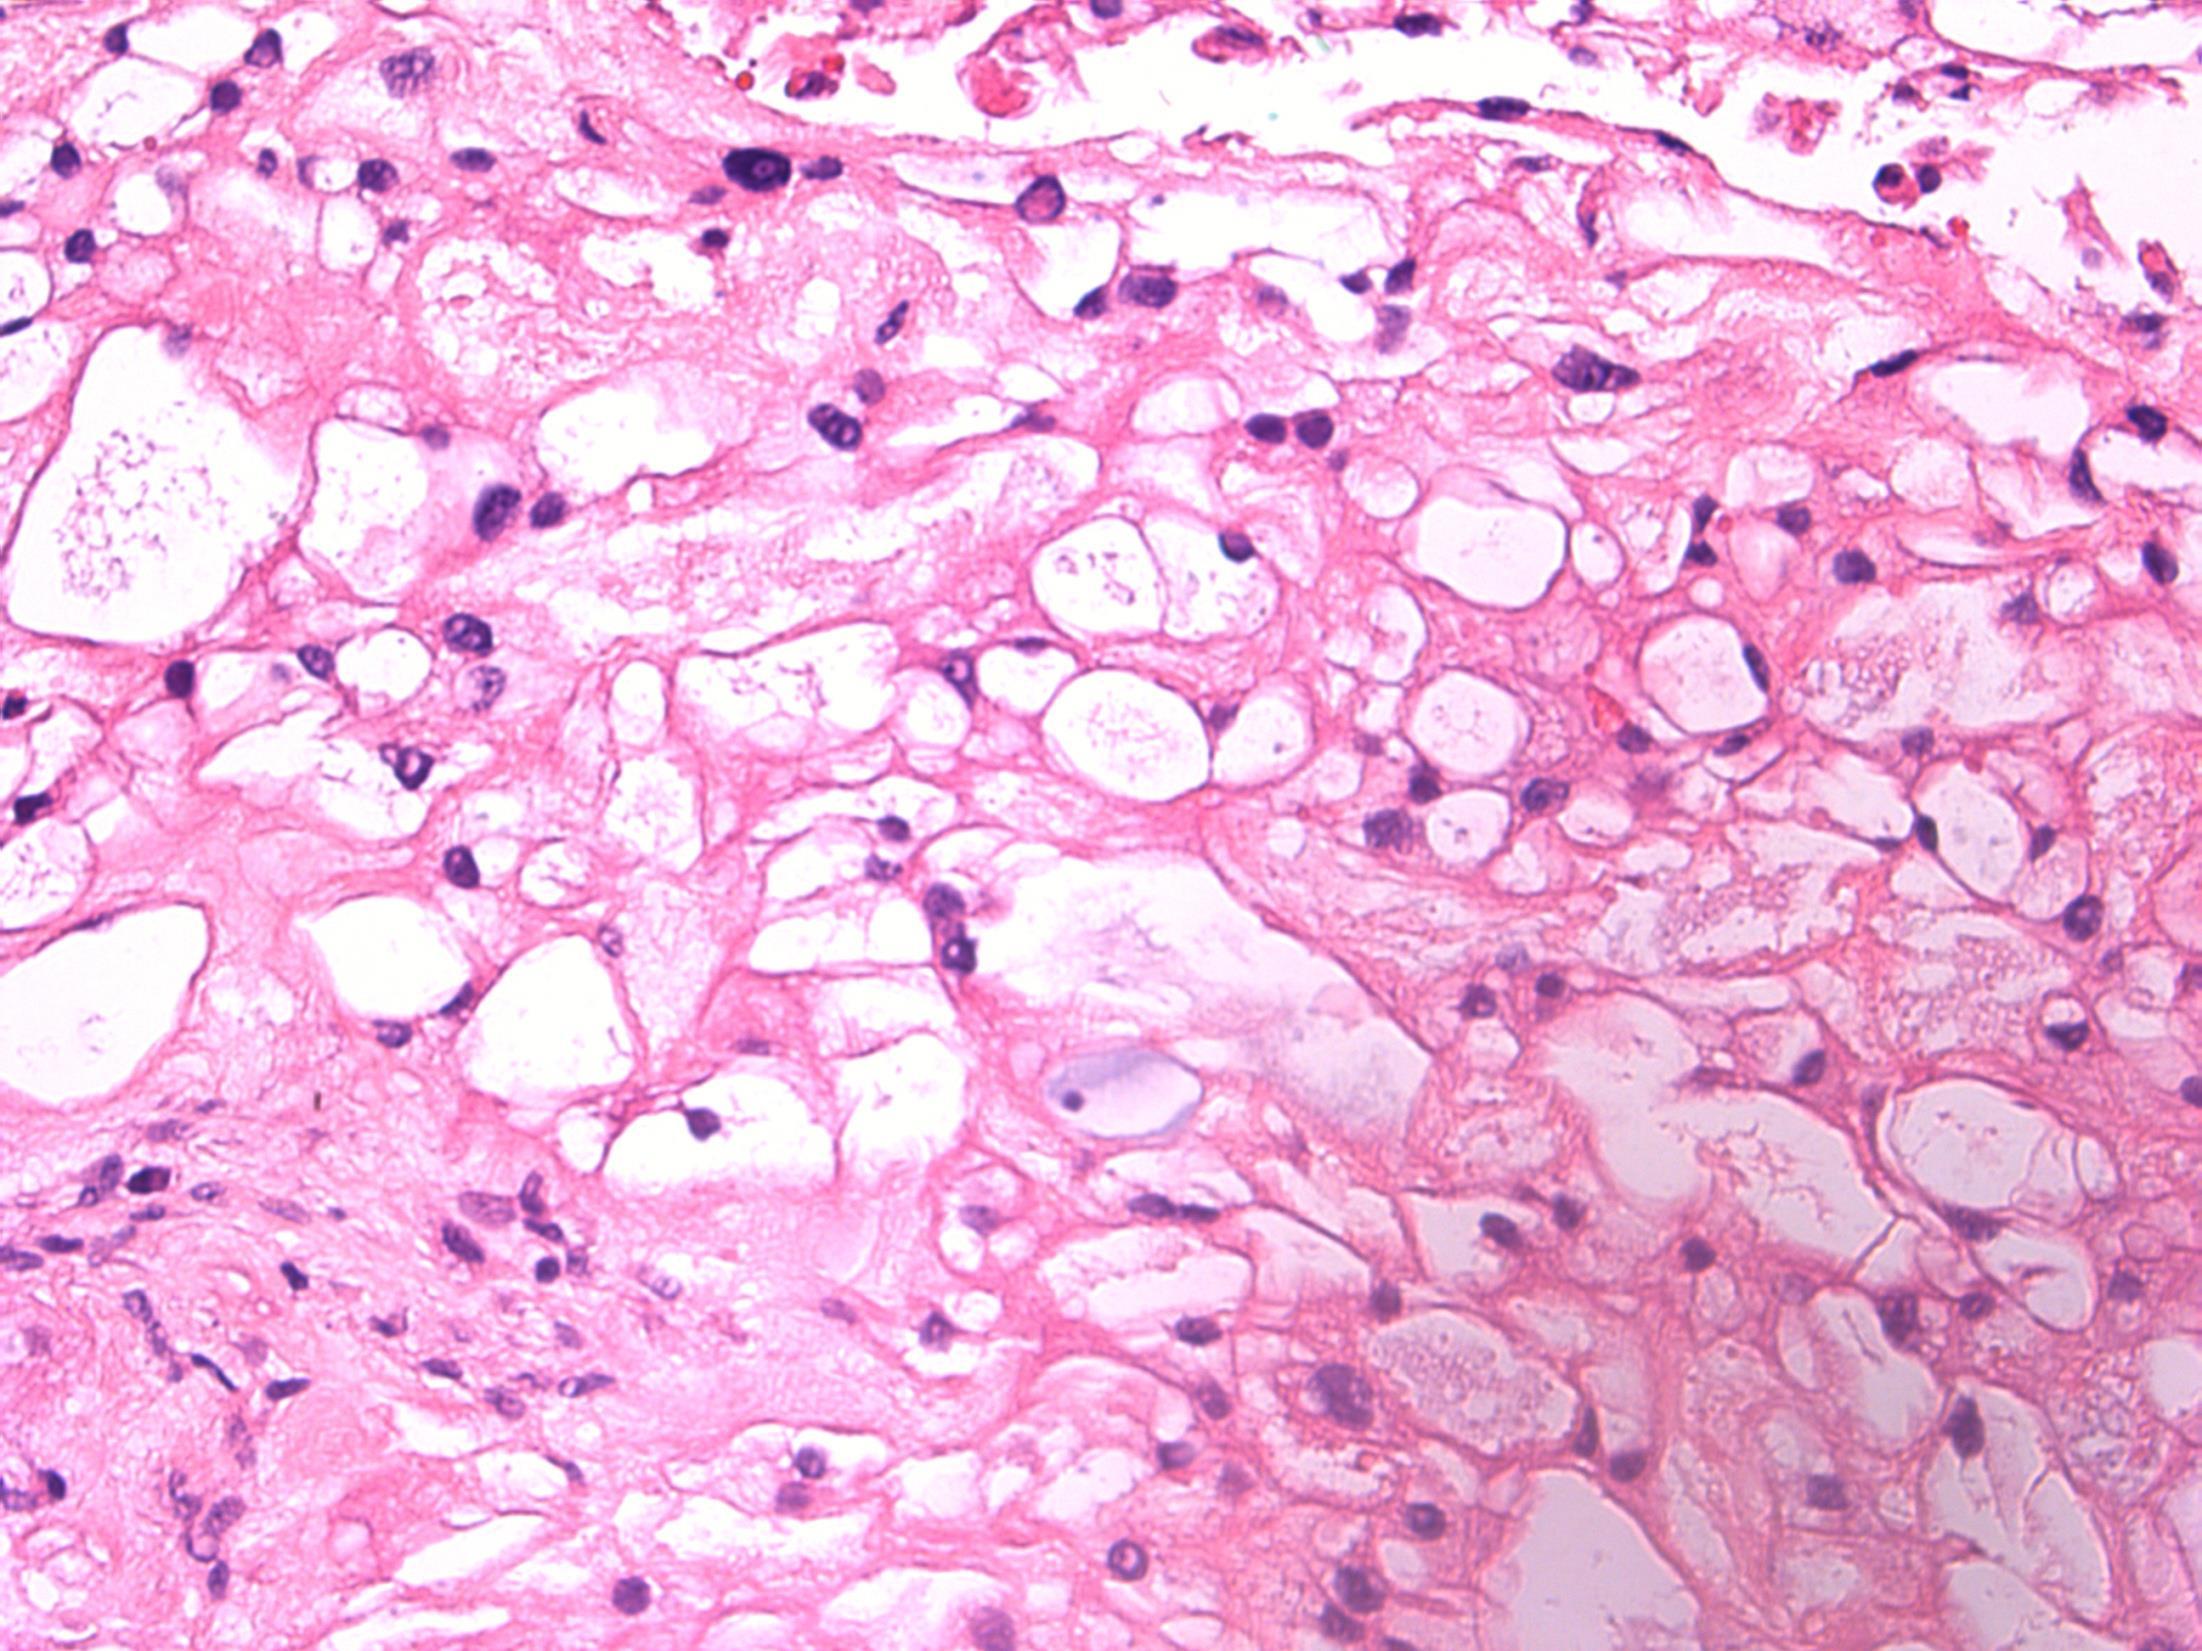

Description: lobulated tumour, physaliferous cells with vacuolated cytoplasm, myxoid stroma, considerable variability. Infiltrates bone. Diagnosis : Chordoma Or Favoured Diagnosis: Chordoma Differential diagnosis • Metastatic carcinoma • Clear cell carcinoma (minor salivary gland) • Lipomatous tumour Plan: IHC- chordoma is S100, vimentin, AE1/3, brachyury positive. Difficult case –Needs expert opinion and clinical/radiological correlation. Comments: Commonest in sacral spine (60%), but spheno-occipital/nasal is second commonest site (25%) like in this case. Low - intermediate malignant potential.